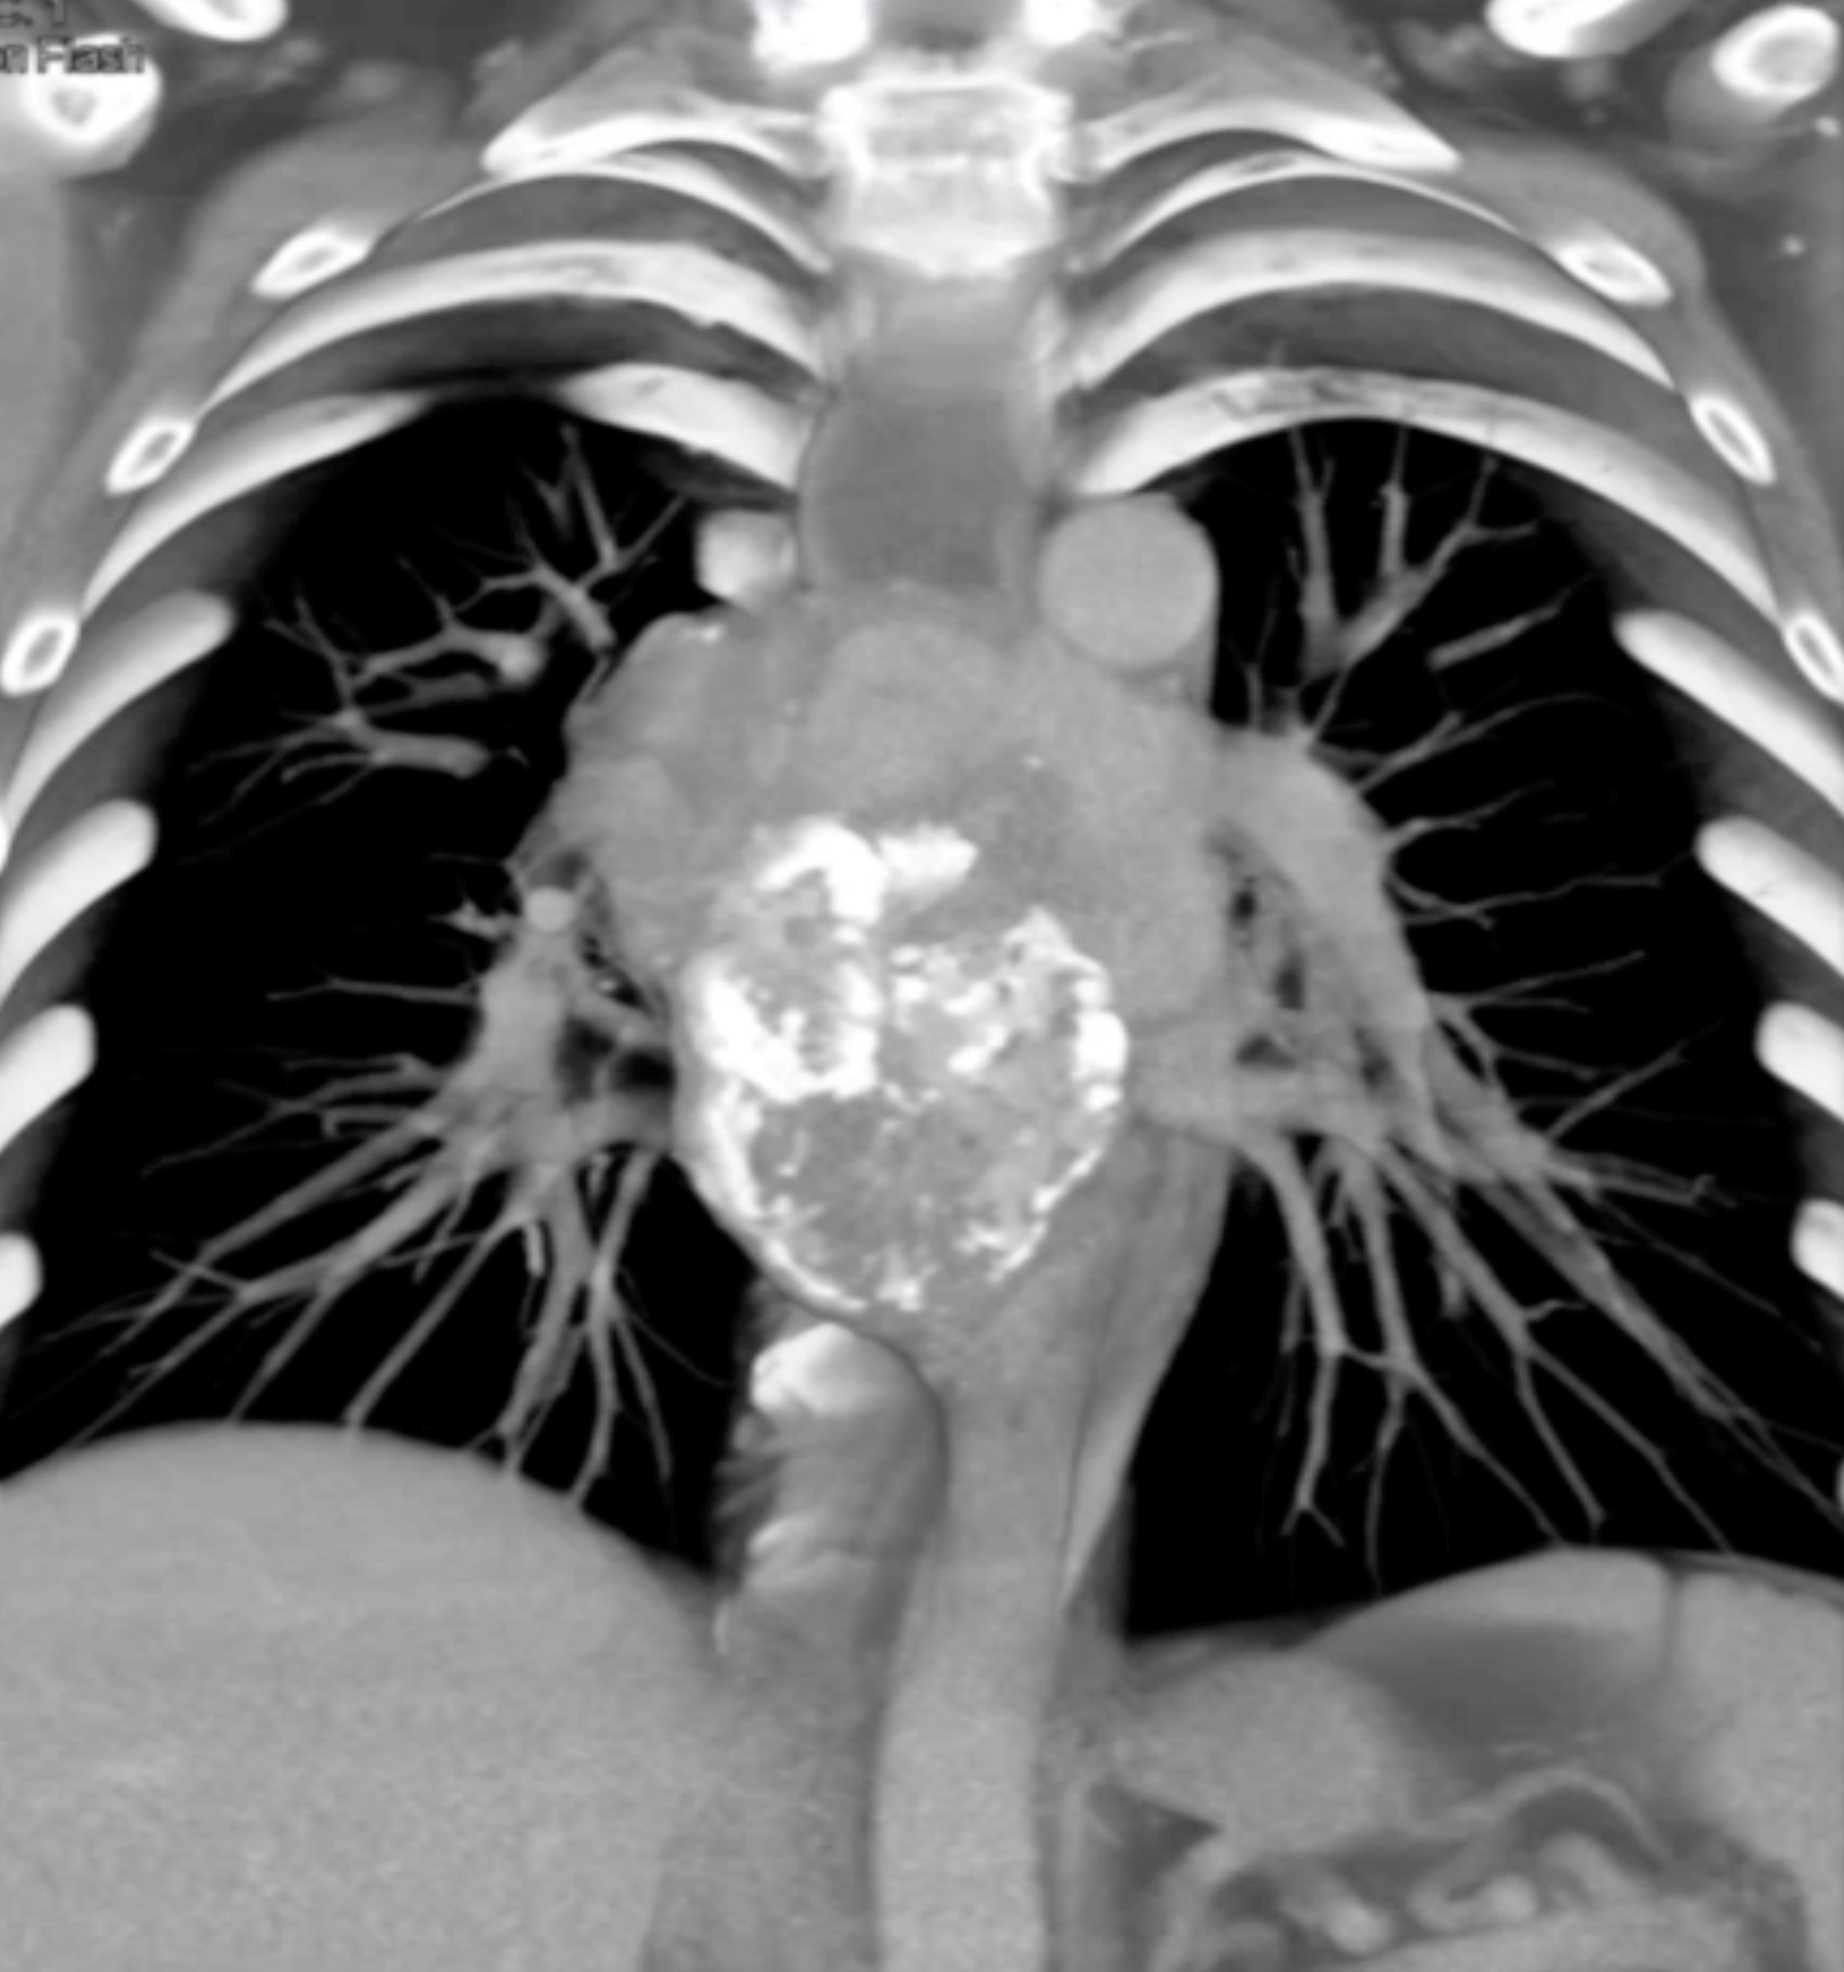

Fibrosing Mediastinitis